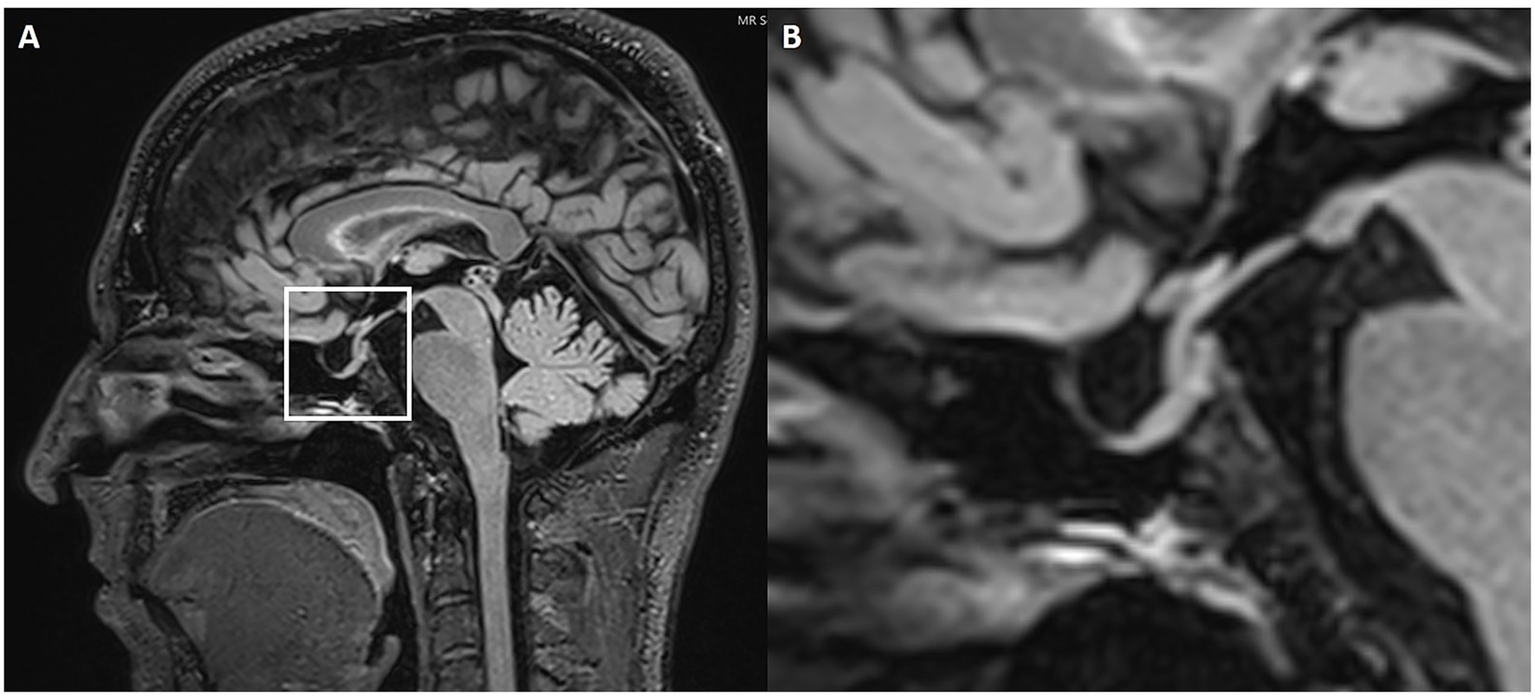

Figure 2

Partially empty sella. Sagittal 3D FLAIR (A) MRI with magnification (B). The white box highlights the sella turcica and pituitary gland. The magnified image shows a slight enlargement of the pituitary fossa, which is filled with CSF.

Figure 3

Enlarged Meckel’s cave. Axial 3D T2w SPACE MRI shows an enlarged left Meckel’s cave with a transverse diameter of 7.3 mm.